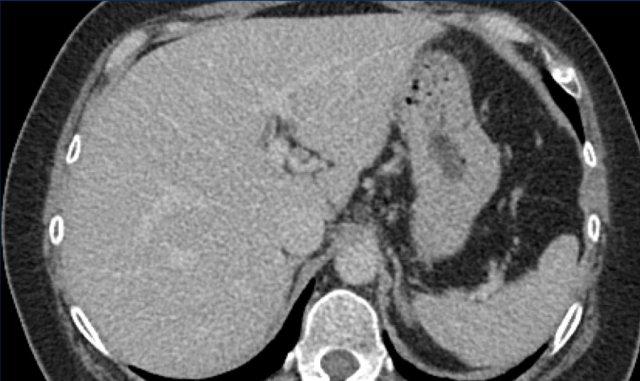

Các hình ảnh cho thấy một tổn thương ngấm thuốc động mạch dạng viền nhẹ ở phân thùy V có thải thuốc.

Có thể thấy một vùng giảm ngấm thuốc dạng tuyến tính kéo dài từ khối u, gợi ý khối u trong tĩnh mạch (mũi tên vàng).

Vì chúng ta không hoàn toàn chắc chắn đây là huyết khối do khối u, nên không thể phân loại trường hợp này là LR-TIV.

Một CT theo dõi được thực hiện, cho thấy tiến triển nặng của khối u cũng như xâm lấn mạch máu vào nhánh tĩnh mạch cửa phải trước (mũi tên trắng).

Lúc này chúng ta có thể xác định chắc chắn sự xâm lấn khối u vào tĩnh mạch cửa.